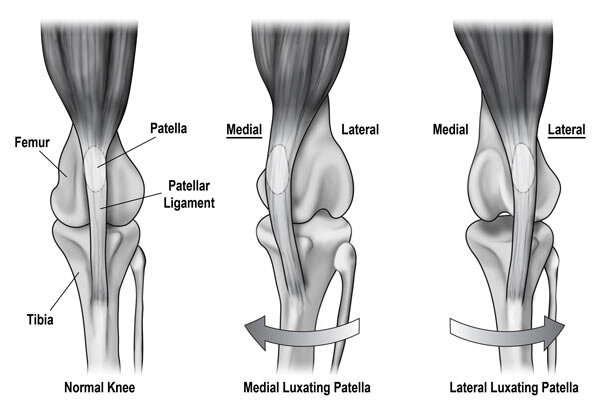

Knee dislocation Wikipedia sale, Knee Dislocation Trauma Orthobullets sale, Knee Dislocation Practice Essentials Prognosis sale, Knee dislocation Wikipedia sale, Luxating patella in dogs PDSA sale, Anterior knee dislocation Radiology at St. Vincent s University sale, Knee Dislocation Trauma Orthobullets sale, Luxating Patella in Dogs Knee Dislocation Symptoms Causes sale, Knee joint dislocations illustrations Radiology Case sale, Dislocated Knee Hartford Hospital Hartford CT sale, Knee Dislocation Practice Essentials Prognosis sale, Knee Dislocation Orthopaedic Trauma Association OTA sale, Knee Dislocation Multi ligament Knee Injuries Lamberti sale, Patellar dislocation Physiopedia sale, Kneecap Dislocation sale, All About Knee Dislocations USF Emergency Medicine sale, Patellar Subluxation Subluxed Partially Dislocated Kneecap Facts sale, Knee dislocation Radiology Reference Article Radiopaedia sale, Posterior knee dislocation Radiology at St. Vincent s University sale, Two years neglected knee dislocation An unusual case report sale, Knee Dislocation Orthopaedic Trauma Association OTA sale, Dislocated Knee Knee Surgeon Minnesota sale, Knee Dislocation Orthobridge Orthopaedic Institute sale, True Knee Patellar Dislocations Core EM sale, Kneecap Dislocation Patellar Subluxation Treatment Symptom Causes sale, Patellar dislocation LITFL Trauma Library sale, Knee dislocation Radiology Case Radiopaedia sale, Patella luxation in dogs Joii Pet Care sale, Medial Patella Luxation Queensland Veterinary Specialists sale, Patella Luxation Warren House Veterinary Centre sale, Patellar luxation Marshalswick Veterinary Surgery sale, Patella Luxation Smart Approach Veterinary Services sale, Patellar luxation Fitzpatrick Referrals sale, Patellar Dislocations Everything You Need To Know Dr. Nabil Ebraheim sale, Medial Luxating Patella Grades of Dislocations Surgery and sale.